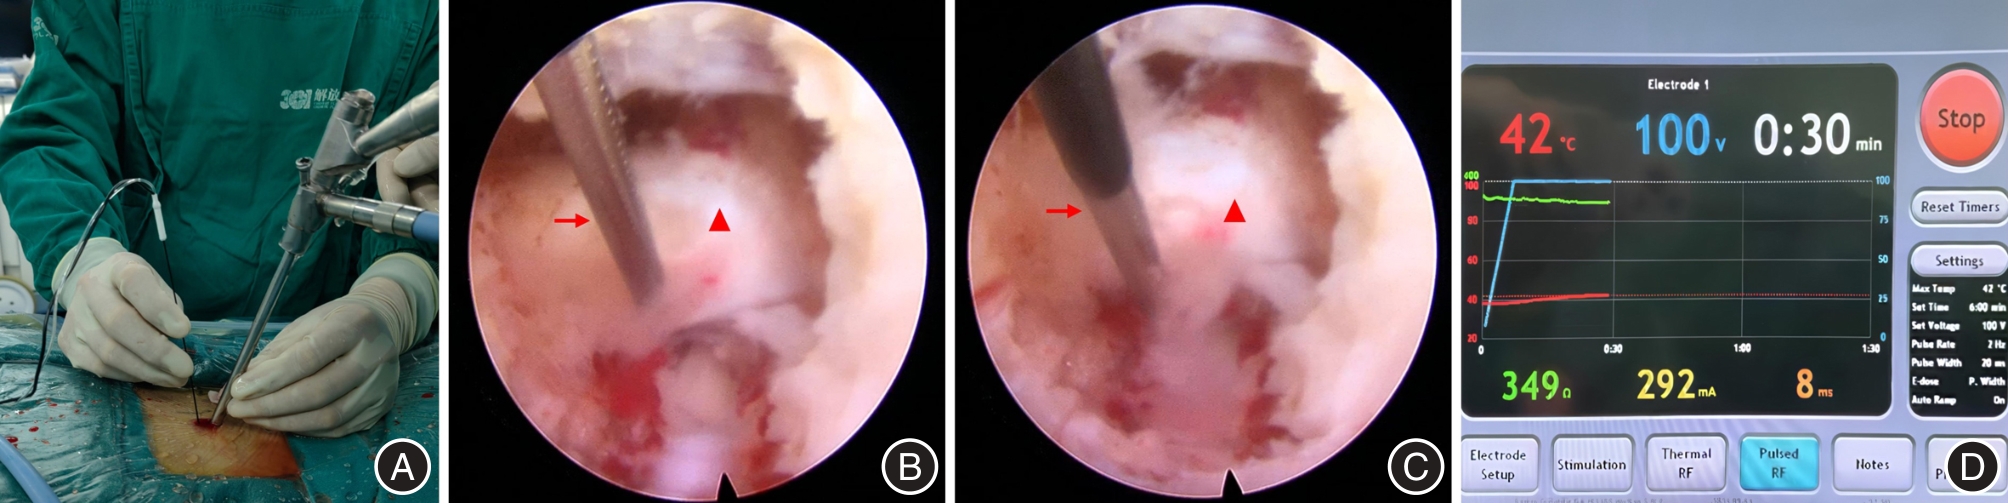

JIANG Q, DING Y, LU Z, et al. Comparative Analysis of Non-Full and Full Endoscopic Spine Technique via Interlaminar Approach for the Treatment of Degenerative Lumbar Spinal Stenosis: A Retrospective, Single Institute, Propensity Score-Matched Study[J]. Global Spine J, 2023,13(6):1509-1521. doi:10.1177/21925682211039181

17 | 蒋强,丁宇,卢正操,等. PE-MFD与Endo-LOVE治疗腰椎间盘突出症疗效比较[J]. 中国骨与关节损伤杂志, 2021, 36 (1): 13-16. |